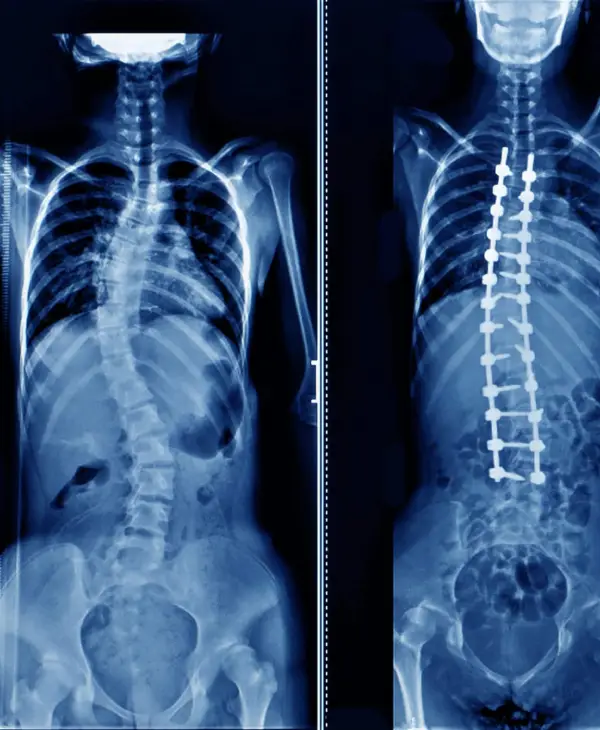

12 year old child with cosmetically and functionally disabling deformity in the back

Diagnosis: Congenital scoliosis with hemivertebra and unsegmented bar

Treatment: Deformity correction with vertebral column resection(VCR) and cage reconstruction

Outcome: child returned to normal life with good self-esteem